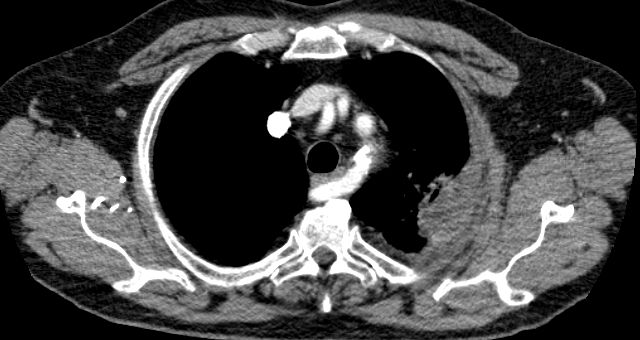

| Supraclavikuläre Lymphknotenmetastase | Lymphknotenmetastase unter der medialen Clavikula

links. ![]() |